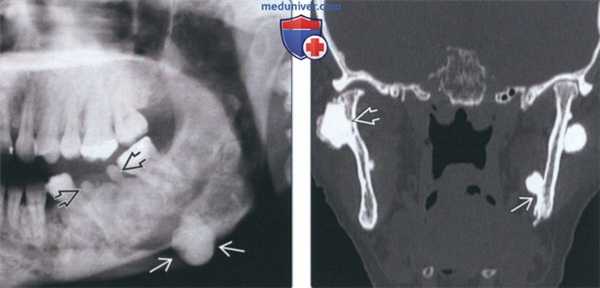

(Слева) На панорамной рентгенограмме у юноши 17 лет в отсутствие каких-либо симптомов определяется образование смешанной плотности в области 1-го моляра нижней челюсти справа -остеобластома (ОБ), очень близко напоминающая цементобластому. Видимая вершина корня отличительный признак. Нижнечелюстной канал смещен книзу.

(Справа) На панорамной рентгенограмме у девочки 13 лет определяется плохо отграниченное просветление под слегка смещенными корнями премоляров нижней челюсти слева и между ними.

2. Рентгенография при остеобластоме челюсти:

• Интра- и экстраоральная рентгенография:

о Опухоль различной рентгеновской плотности:

- Опухоль, вплотную прилежащую к корню зуба, можно спутать с цементобластомой или периапикальной патологией, особенно при наличии болевой симптоматики:

Проба на жизнеспособность и отсутствие явной причины (кариес/перелом) помогают исключить патологию пульпы

о Возможно смещение или резорбция корней зубов

3. КТ при остеобластоме челюсти:

• КЛКТ и КТ в костном окне:

о Может обнаруживаться вздутие

(Слева) На КЛКТ(профильный срез) у этой же пациентки структура ОБ выглядит зернистой. Обратите внимание на поражение язычной и щечной кортикальных пластинок в отсутствие вздутия.

(Справа) На аксиальной КЛКТ у этой же пациентки определяется поражение кортикальных пластинок опухолью с однородной зернистой структурой. ОБ челюстей обнаруживаются преимущественно в теле нижней челюсти; их рентгеновская плотность варьирует (рентенонегативное образование-опухоль смешанной плотности с множественными кальцинатами).

На ортопантомограмме определяется обширная рентгенопрозрачная зона, затрагивающая второй нижний моляр с правой стороны. Образование содержит кальцифицированные массы, приближающиеся к дистальному корню второго моляра, а так же несколько рентгеноконтрастных участков, расположенных на фоне зоны просветления. Данное образование являлось хорошо очерченным и вызывало выбухание и истончение костной ткани нижнего края нижней челюсти. (Фото 1).

Фото 1: Ортопантомограмма. Крупное однополостное рентгенопрозрачное образование, затрагивающее второй нижний моляр с правой стороны, с участками минерализации